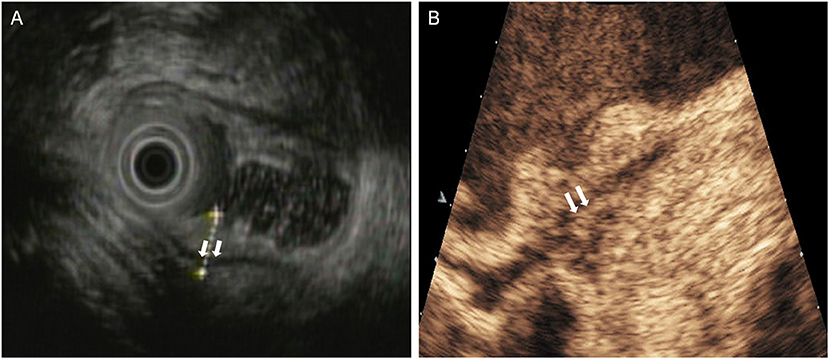

Figure 5. A case with T1 tumor was overstaged by DCEUS but was accurately staged by EUS. (A) EUS showed a lesion invaded into the submucosa, and the muscularis propria was intact (arrow), but (B) DCEUS showed the lesion invaded into the muscularis propria (arrow) in error and overstaged it as T2 tumor.

In this study, the overall accuracy of DCEUS was similar to that of EUS in determining the T stage. But EUS was superior to DCEUS for T1 stage and DCEUS was superior to EUS for T3 and T4 stage. EUS is used to visualize the lesion surface, portraying interference of abdominal fat and gas in the stomach. Thus, EUS is more accurate in identifying stages early in well-differentiated carcinomas (Figure 5) (36). The accuracy of EUS in late stage tumors was reduced. A lesion-by-lesion analysis revealed that overestimation of EUS mostly present in the cases of malignancy with ulcerative type. Using EUS it is difficult to differentiate fibrosis and inflammation from tumors, which is a common cause of misreading of depth in ulcerative malignancy. Moreover, we found underestimation of invasion depth mostly present in the cases of tumors with diameters >5 cm. This maybe due to the tumors being too large and the frequency of EUS being relatively high, it was hard for EUS to display the whole lesions or to show the views of the maximum depths of infiltration (Figure 6). Contrariwise, DCEUS is better for determining the stage of advanced gastric cancer due to the rich blood supply. The advantage of DCEUS is its high contrast resolution, which can be used to distinguish tumors from normal tissue. Hence, it is sensitive to lesion detection, characterization, and staging. What's more, it can show the relationship of the lesion's vasculature and the gastric wall, in addition to their contours. The lack of vascularity in early gastric cancer leads to its low accuracy. In addition, other factors may also influence its accuracy, such as unsatisfied filling of gastric cavity, artifacts caused by gastric peristalsis.